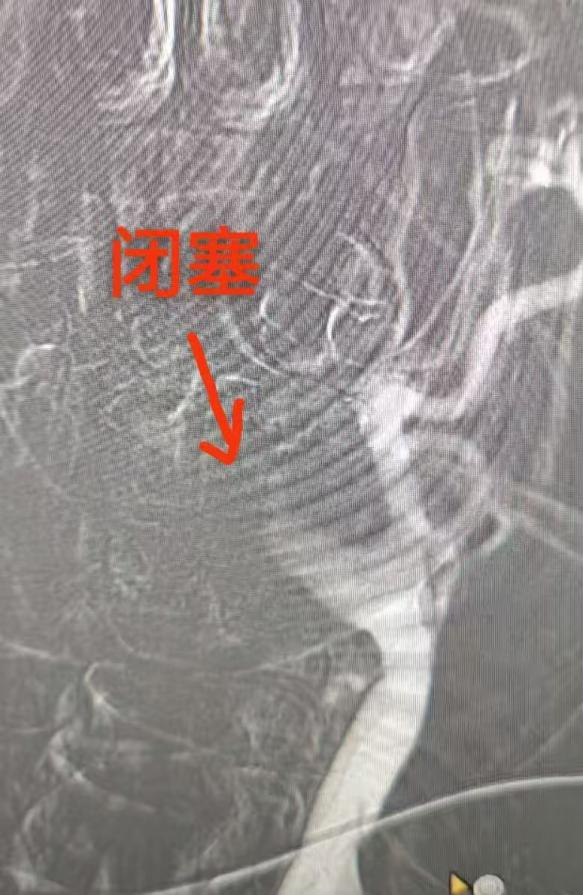

授权即行动!卒中中心绿色通道全程开启,患者第一时间接受静脉溶栓。与此同时,肖科金主任与朱胜华副主任医师迅速开展急诊血管内介入手术。造影证实“左侧颈内动脉急性闭塞”,团队立即行颈动脉再通,利用微导丝、球囊精准开通血管。术后影像显示:血流恢复通畅!